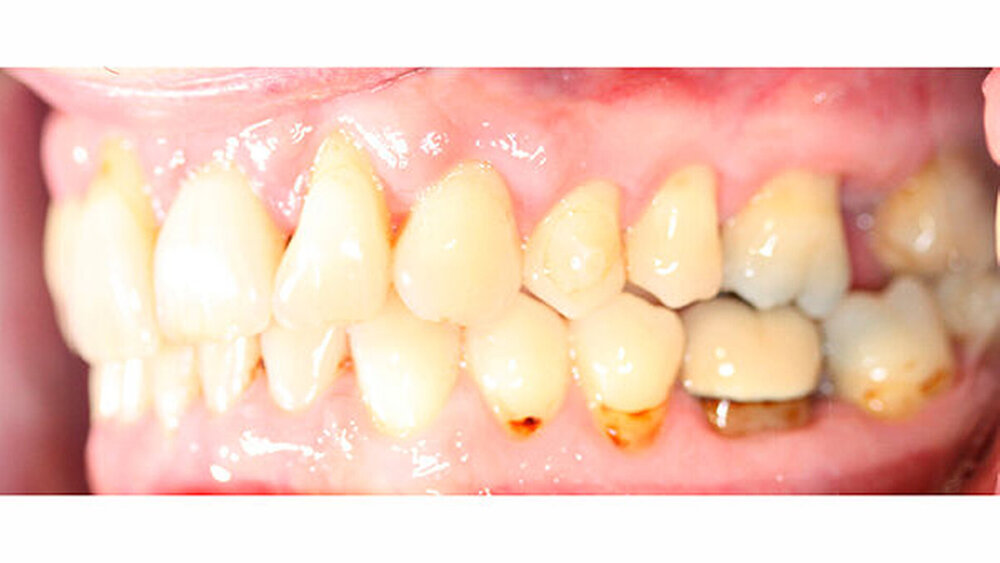

Nach erfolgter Parodontitistherapie und konservierender Versorgung stellte sich der Patient Ende 2014 erneut in unserer Praxis vor.

Die Sulkustiefen konnten auf etwas weniger als 4 mm reduziert werden, während der Blutungs- und Plaque-Index bei weniger als 15 Prozent lag. Daher wurde eine kieferorthopädische Behandlung über die nächsten zwei Jahre in Kombination mit engen zahnärztlichen Kontrollen geplant. Als Mittel der Wahl entschieden wir uns gemeinsam mit dem Patienten für das Invisalign-System, da hiermit sowohl eine Schienung als auch eine kraft-arme Bewegung der Zähne möglich sein sollte. Für den Frontzahnbereich wurden keine Attachments geplant, so dass hier eine unnötige Hebelwirkung umgangen werden konnte (Abbildung 3).